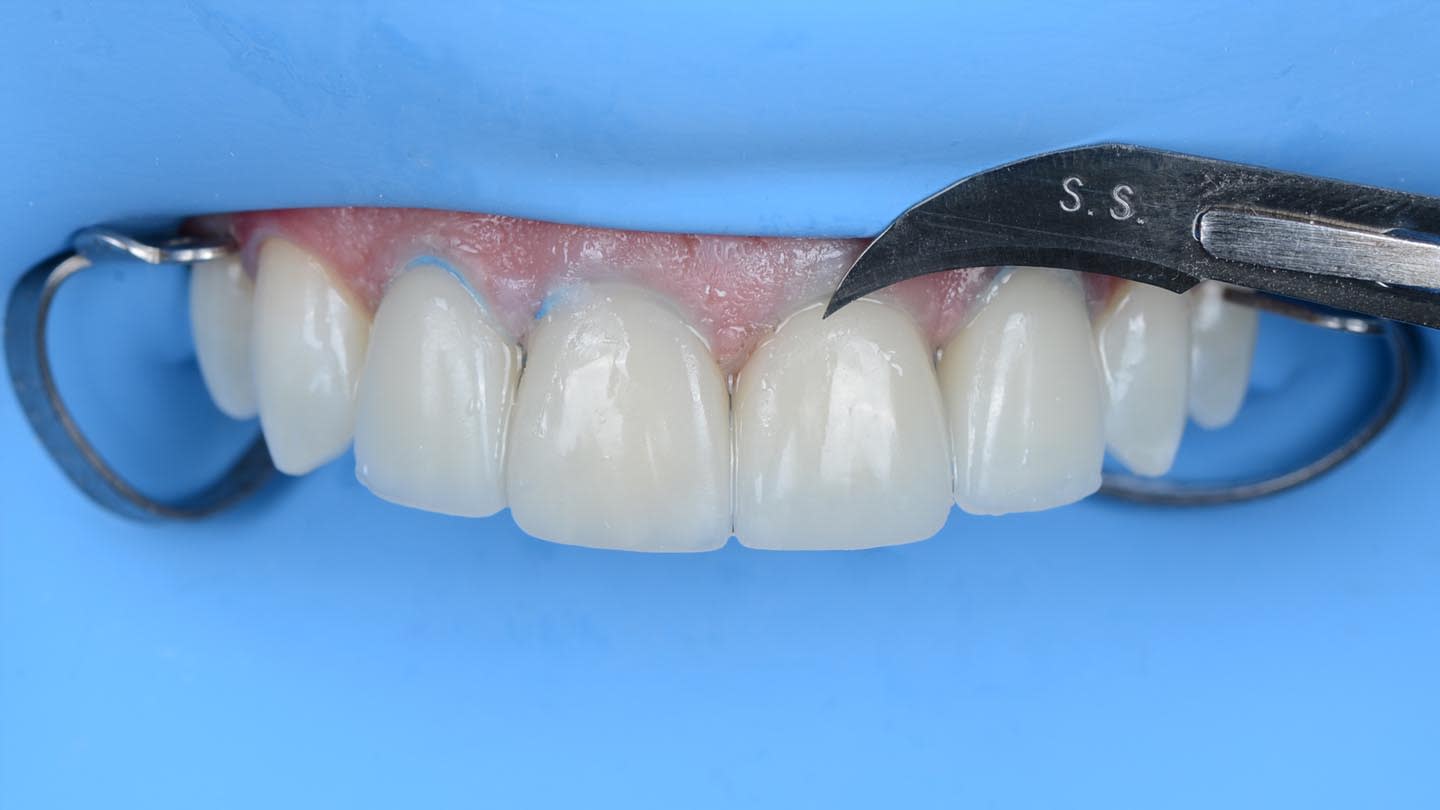

Rubber dam was used when bonding the final restorations. The veneer corresponding to tooth No. 9 was initially bonded to the opaque-core crown extraorally following standard protocol for silica-based ceramics,19 which included 9% hydrofluoric acid-etching (Porcelain Etch, Ultradent, ultradent.com), silane application (Monobond Plus®, Ivoclar), and application of a light-curing resin cement (Variolink® Esthetic LC, neutral shade, Ivoclar) (Figure 9 through Figure 13).

Next, the combined restoration was inserted into tooth No. 9 intraorally using a self-curing resin cement (Multilink Automix®, opaque white, Ivoclar) according to the manufacturer’s instructions. The try-in paste was always used prior to cementation to help predict the influence of the resin cement shade on the definitive restorations. For this case, white opaque cement exhibited good masking ability, especially in the cervical area. The remaining veneers were bonded with the same light-curing resin cement used in the initial bonding stage for tooth No. 9. A neutral shade was used to avoid influencing the final color of the restorations (Figure 14 through Figure 17).